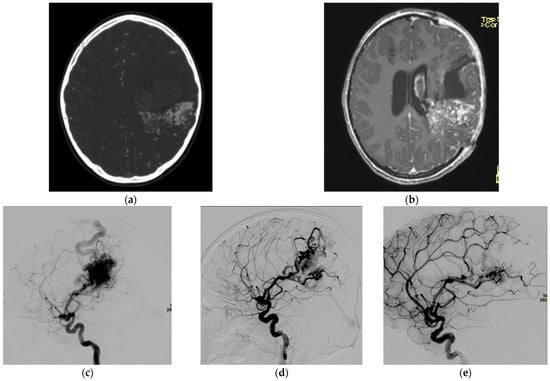

2.1.1. Arteriovenous Malformations